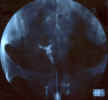

| Cavité utérine de petite taille, en forme de T. Aspect légèrement rétréci du segment inférieur. Sténose annulaire de la corne droite. Perméabilité tubaire bilatérale.

|      |